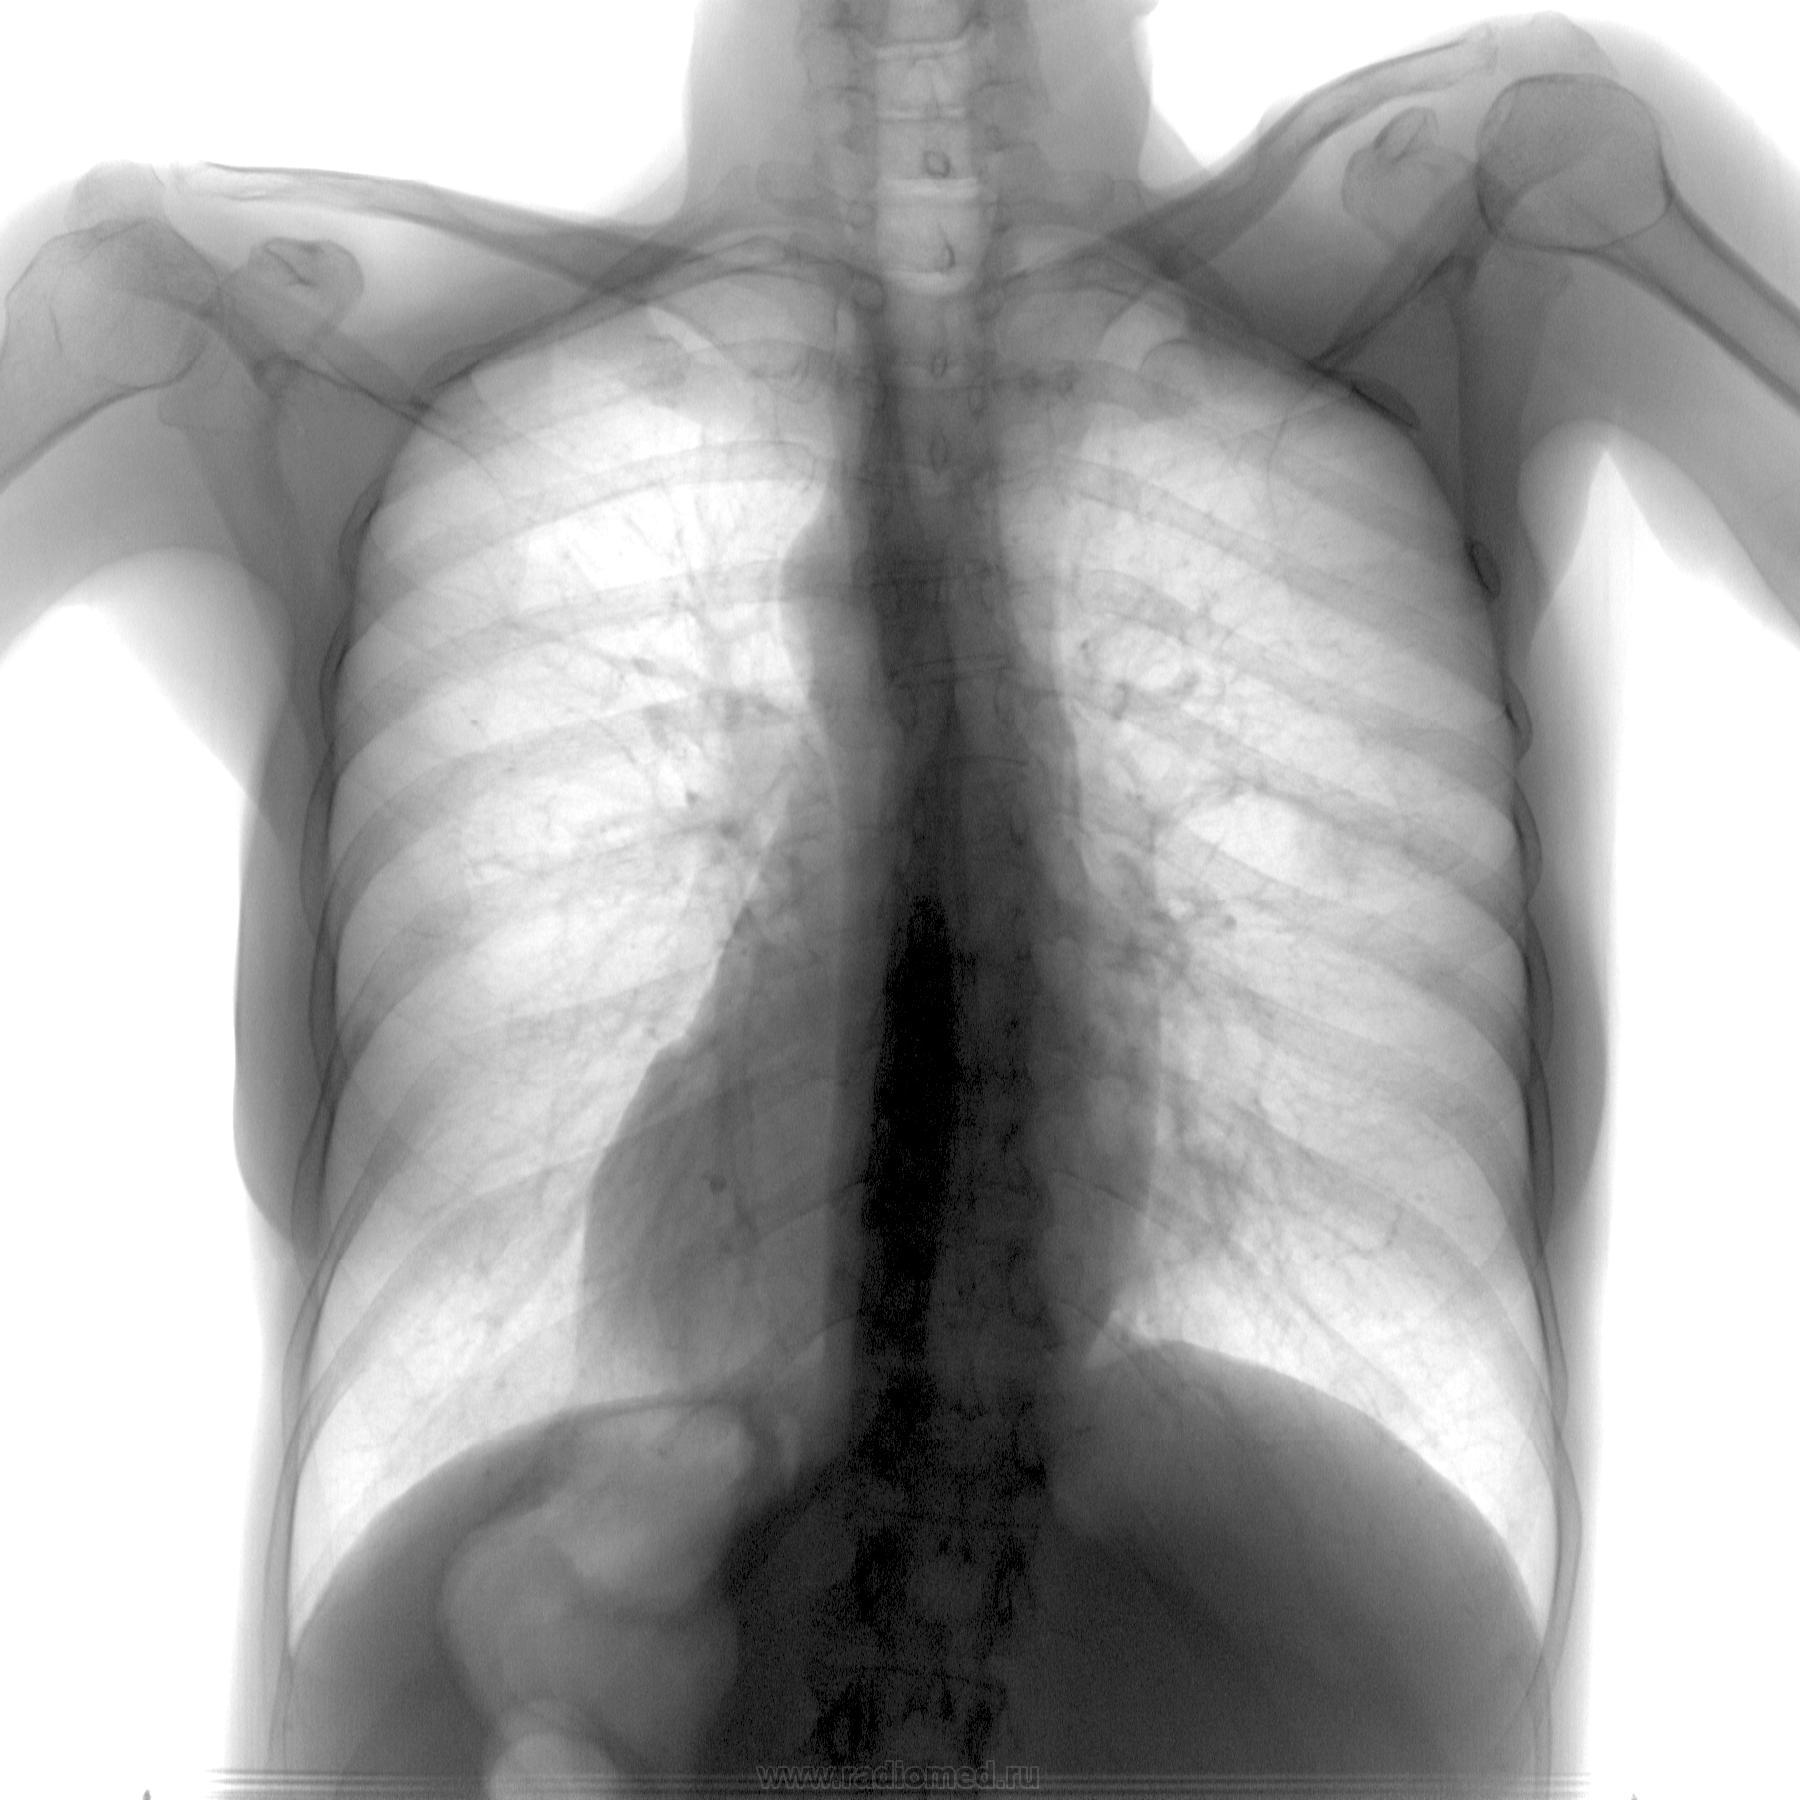

Но инфильтрат есть и в среднем отделе! А как Вам их форма, не "круглит"?

"Круглит"... А леч.врач ничего не говорит? Клиника, кровь, там неизвестно ничего ? Что ж, с нетерпением будем ждать ПН

Форма действительно круглая.

Это то меня и "смутило". У этой истории есть продолжение...но...только в понедельник уже.....

в дифф. диагноз добавил бы туберкулему.

Вообще, вижу две округлые тени. Вторая в 10 сегменте.

Вобщем мне тоже тени "показались" курглыми. Учитывая это, "смазанную" книку воспалени для исключения метастатического поражения была проведена КТ.

Вот снимок из архива за 2012 год и несколько самых показательных слайдов КТ за 2013 год (через дней пять-семь после ФГ)

Не было бы у меня сомнений на счет описания, не стал бы и случай выставлять)))..... "пневмония? рак?" - где то так примерно))))